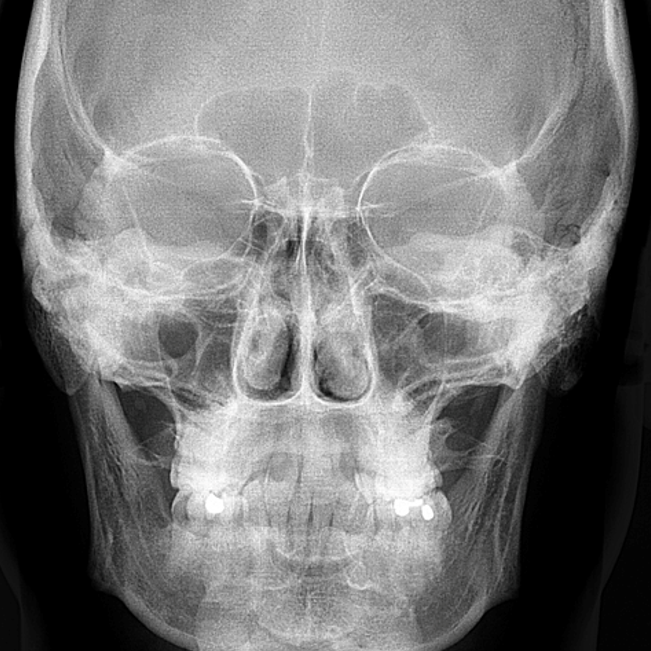

É uma radiografia que permite a visualização dos ossos da face e do crânio, possibilitando a avaliação do crescimento e desenvolvimento, relação maxilo mandibular, simetria, estudo de adenoide, processos patológicos e traumáticos. Bastante utilizado em planejamentos cirúrgicos e ortodônticos.